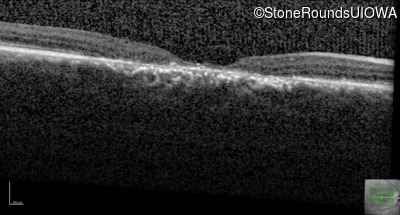

Age at visit: 29 years

This 29-year-old man had good vision until his early 20's. at which time he began to experience a slow reduction in his acuity. His driver's license was restricted at age 27.